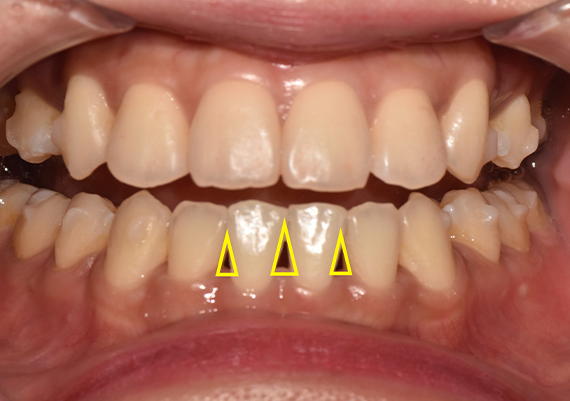

치아 사이사이에 존재하는 빈 공간,

치과 용어로는 흔히 ‘블랙 트라이앵글’이라고 부르는 현상에 대한 것입니다.

실제 환자분들 입장에서의 블랙 트라이앵글 현상은

심미적으로 보기 좋지 않다는 이유에서 고민이 되는 일이 많은데요.

다음 두 번째 문제로는 위생 문제를 예로 들 수 있는데요.

잇몸이 미처 채워지지 않아 발생한 빈 공간에는

그만큼 또, 작은 음식물 잔사가 더 쉽게 자주 끼이게 됩니다.

따라서 블랙 트라이앵글이 있는 치아는

이와 같은 현상이 없는 치아에 비해

치주 질환에 취약해집니다.